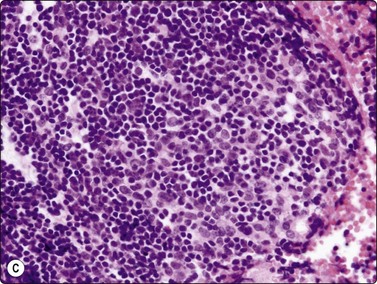

Fig. 9.1 Thymoma, lymphoepithelial

(A) Cohesive fragments of tumor tissue in a background of lymphoid cells (Pap, LP); (B) Cohesive cluster. Epithelial cells visible centrally Pap HP; (C) Cell block, indistinct epithelial cells (H&E, HP); (D) Cell block, reticular pattern of epithelial cell staining for AE1+3 keratins (IPOX, LP).

Tissue section; biphasic cell population (H&E, HP).

The histologic classification of thymomas is complex, evolving, and still somewhat controversial. Such subclassification may prove challenging for the histopathologist and this is exaggerated with aspiration cytology. Clearly, there is a wide spectrum in the cytomorphology of thymomas. First, there is a broad range of appearances of benign thymoma cells among and even within some of these neoplasms; this is complicated by the varying proportions of lymphocyes present.

In the benign thymomas, the epithelial cells are usually cohesive (Figs 9.1, 9.5) but may also manifest a reduction in intercellular cohesion (Fig. 9.2). Epithelial cells are not immediately evident in the mixed tumors at low power but are discernible using the higher magnification.18,29,30 The epithelial cells are polygonal, oval, or spindle shaped with uniform to slightly irregular nuclear outlines possibly with cleaved or folded nuclei. Their nuclear chromatin is homogeneous, finely distributed and pale and, occasionally, small nucleoli are seen. Cell borders are indistinct, but nuclei are separated by moderate amounts of pale cytoplasm (Figs 9.2, 9.5). In one personally examined case of thymoma metastatic to lung, Hassall’s corpuscles were evident in the clumps of tumor cells (Fig. 9.4); this is a most unusual manifestation and will not be present in most thymomas. When there is a lymphoid population, the bimodal pattern enables one to make a virtually certain diagnosis.18,29,30 In pure epithelial or spindle cell forms, definitive diagnosis is more difficult, although in Dahlgren’s series29 most thymomas were diagnosed and in Tao’s 37 cases30 all FNAC diagnoses of thymoma were verified histologically. Ali and Erozan34 were able to diagnose all of their 14 cases using a combination of cytology, immunocytochemistry and clinical information, and Shin and Katz showed a high accuracy in a range of mediastinal lesions including 14 thymomas.35 Tao and others describe more variation in the degree of cohesion than we have seen, particularly in pure epithelial/nonspindle cell types.30 Overall, the most challenging and the most common in our experience are the lymphocyte-rich (type B1) thymomas, as the tumor cells may be obscured by the lymphocytes.